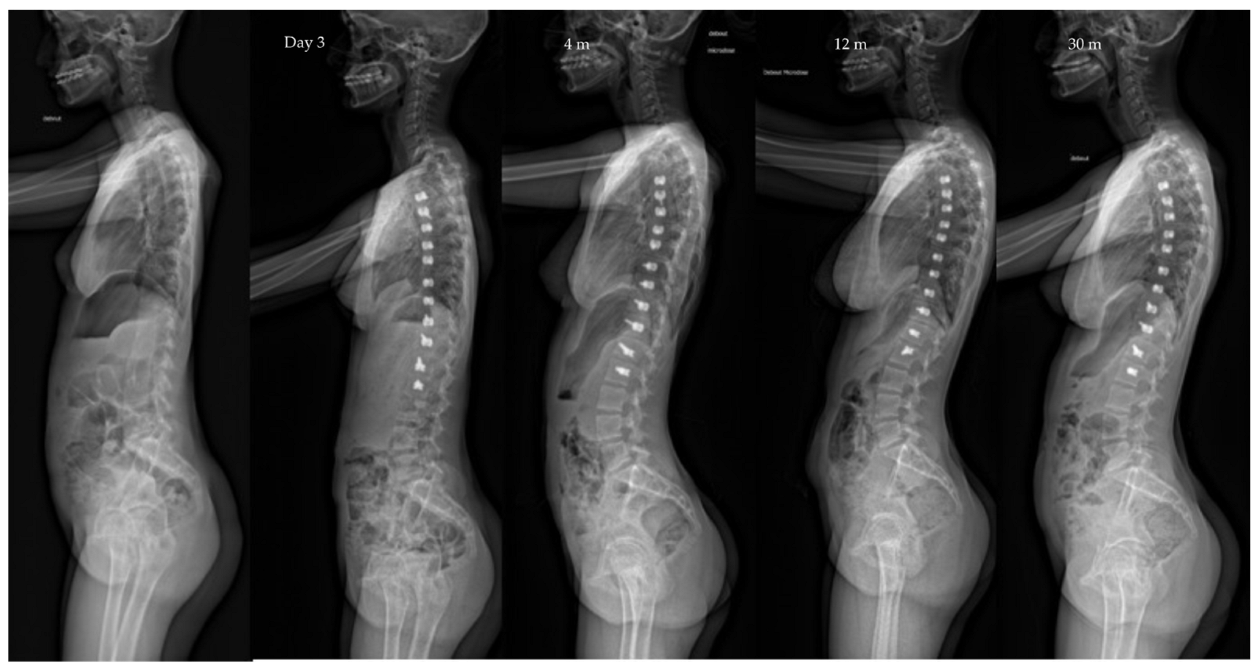

| Pre-op | Post-op Day 3 | Post-op 1y | Last f/u | p-Value | |

|---|---|---|---|---|---|

| Major curve | 49°(8,9°) | 27°(12°) | 22°(12°) | 19°(14°) | <0.01 |

| Secondary curve | 27°(14°) | 23°(15°) | 22°(11°) | 17°(10°) | <0.01 |

| Instrumented curve | NA | 26°(11°) | 23°(10°) | 20°(14°) | <0.01 |

| Kyphosis (T1–T12) | 20°(13°) | 23°(13°) | 25°(12°) | 24°(14°) | 0.06 |

| Lordosis (L1–L5) | 36°(12°) | 32°(13°) | 40°(7°) | 40°(8°) | 0.07 |